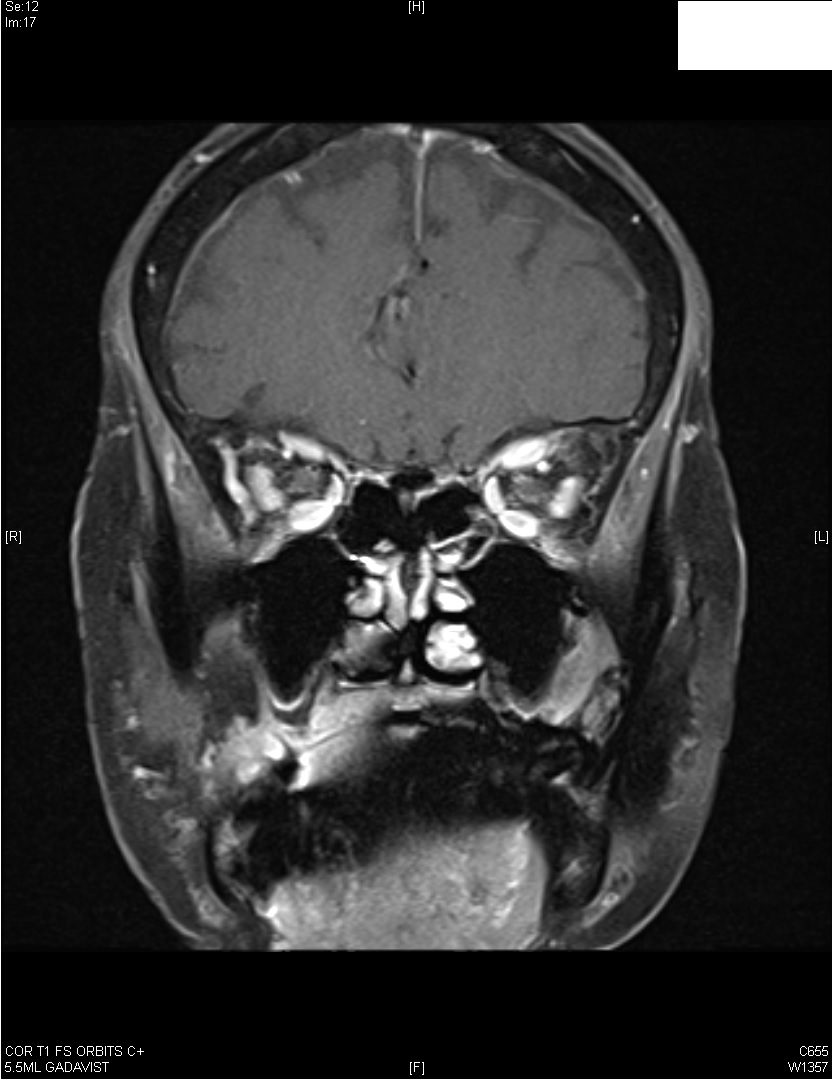

A 84-year-old right handed lady presented with 2 months history of diplopia on binocular vision worse on right gaze. On monocular vision, diplopia disappeared irrespective of which eye was closed. AchR binding Ab was 1.07 nmol/L (positive >0.5 nmol/L) and she was diagnosed with myasthenia gravis. Neurological examination was normal. Nerve conduction studies and needle EMG of all muscles was within normal limits. Repetitive nerve stimulation at 3 Hz of the left medial nerve/APB and accessory nerve/trapezius system, at rest and following 10 seconds and 60 seconds of exercise revealed no abnormal decremental or incremental response (figure 1). MRI brain revealed enlargement and abnormal enhancement of the muscle bellies of the bilateral superior, medial and inferior rectus muscles in pattern suggestive of thyroid orbitopathy (figure 2).TSH 3rd generation was 0.145 (range 0.550-4.780 uIU/mL. Thyroid associated orbitopathy, also known as Graves’ orbitopathy, is typically a self-limiting autoimmune process associated with dysthyroid states with clinical presentation varying from mild disease to severe irreversible sight-threatening complications. 1